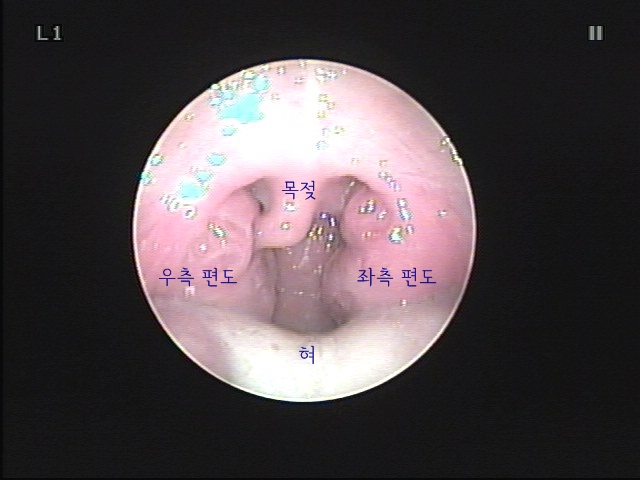

- 진찰은 먼저 육안으로 편도 상태를 관찰하고 후두 내시경을 통해 편도 깊숙이 관찰합니다. 진찰 중에 관찰되는 결석은 그 자리에서 최대한 제거하도록 되어 있습니다.